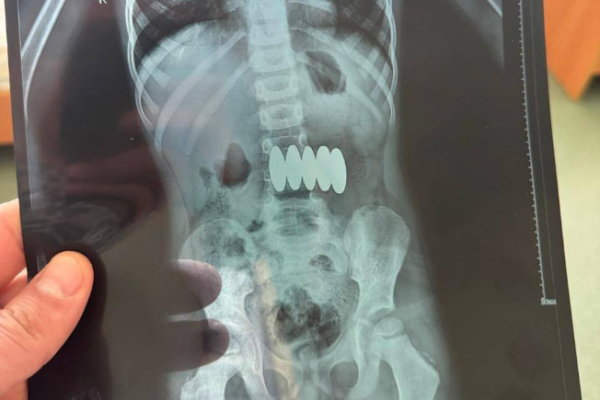

В Черкасах лікарі врятували 5-річного хлопчика, який проковтнув кілька магнітів із популярного магнітного...